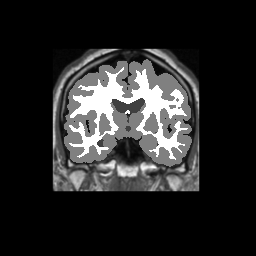

Accuracy is reported as Dice overlaps between a tool's segmentation and the Internet Brain Segmentation Repository (IBSR) manual segmentation for each of the 18 IBSR subjects. The inter-tool comparison (on the left below) shows the median Dice coefficient for each tissue class. The overlaps for FSL (from which the median values are drawn) are shown in the plot on the right.

Subject Accuracy (IBSR)

Overlap coefficients for each tissue class are shown here for each IBSR subject. Select a subject below to see the FSL results compared to other tools.